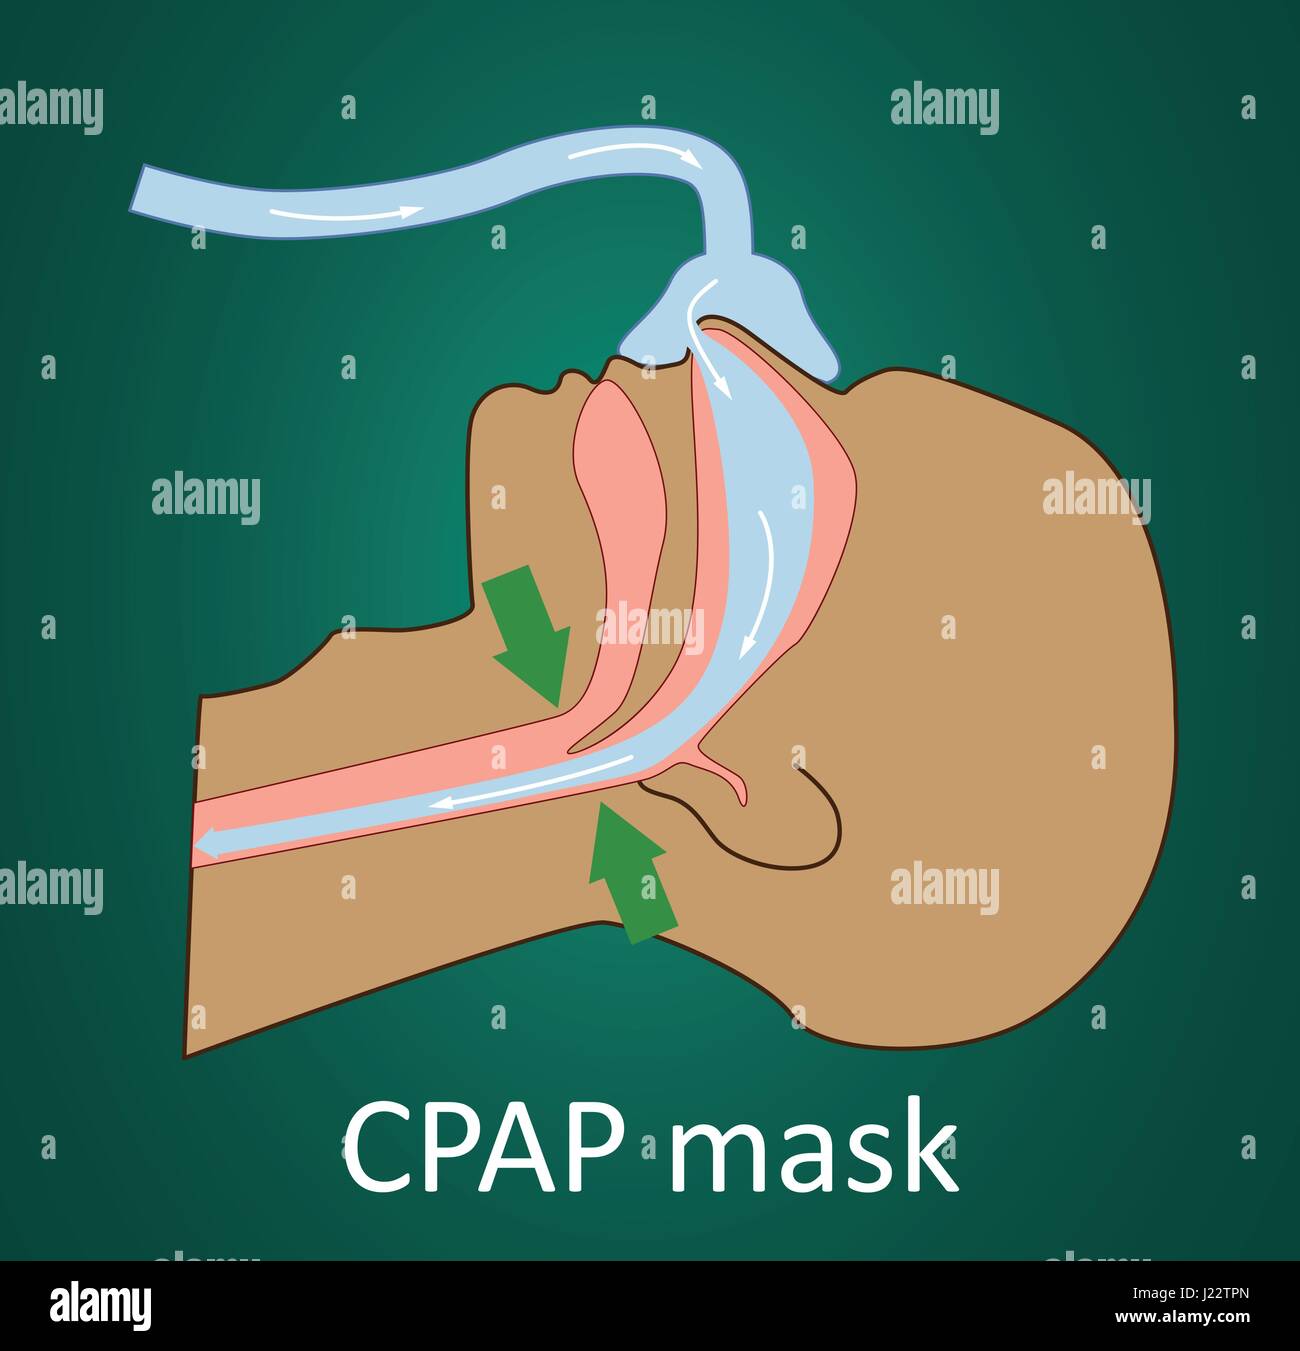

Vector illustration of normal breathing with CPAP mask. Stock Vectorhttps://www.alamy.com/image-license-details/?v=1https://www.alamy.com/stock-photo-vector-illustration-of-normal-breathing-with-cpap-mask-138975613.html

Vector illustration of normal breathing with CPAP mask. Stock Vectorhttps://www.alamy.com/image-license-details/?v=1https://www.alamy.com/stock-photo-vector-illustration-of-normal-breathing-with-cpap-mask-138975613.htmlRFJ22TPN–Vector illustration of normal breathing with CPAP mask.